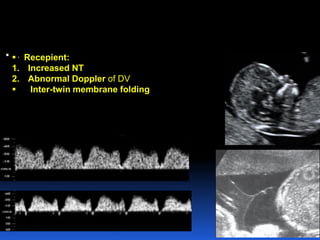

1. Recipient:

Increased nuchal translucency

Abnormal Doppler of DV

2. Folding of intertwin membrane can at 16w.

 . Recepient:

1. Increased NT

2. Abnormal Doppler of DV

 Inter-twin membrane folding